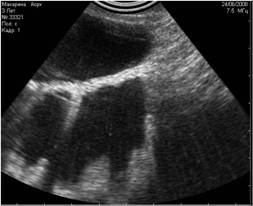

Рис. 27. Рефракция в этом случае имитирует прерывание целостности диафрагмы. |